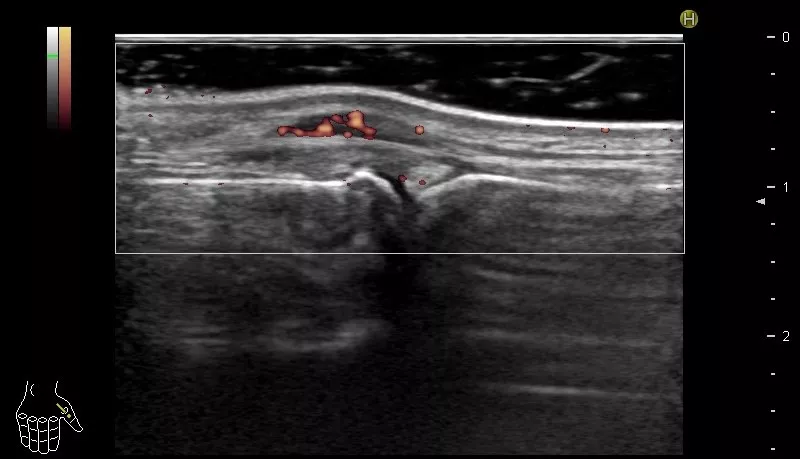

身体所見では手指関節炎、下腿浮腫、右頬部に紅斑を認めた。血液検査で抗核抗体陽性、抗DNA抗体高値、補体低下、尿たんぱく陽性、リウマチ因子陰性、抗CCP抗体陰性。手指関節X線では、2-5指中手指節間関節の掌側脱臼を認めるが、骨には異常を認めない(写真2)。関節超音波検査では、腱鞘滑膜炎を主体とする炎症を認めた(写真3)。尺側偏位や掌側亜脱臼は、関節リウマチの変形として有名であるが、全身性エリテマトーデスでも関節炎が強い症例では同様の変形を認めることがある。これをJaccoud関節炎と呼ぶが、強い亜脱臼や脱臼、腱拘縮による変形にも関わらず、骨破壊は認めないのが特徴である。本症例は、リウマチ因子陰性、抗CCP抗体陰性で、否定はできないが関節リウマチの可能性は低い。手指関節炎、抗DNA抗体上昇、補体低下、尿たんぱく陽性所見から、ループス腎炎を伴う全身性エリテマトーデスの再燃が疑われ、関節変形も、全身性エリテマトーデスによるJaccoud関節炎に起因すると診断した。

写真3